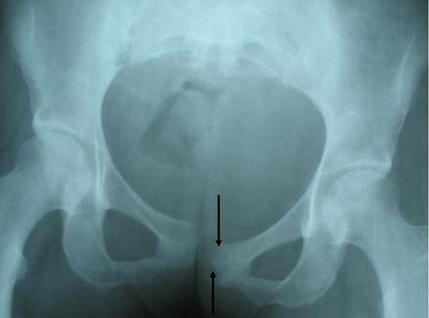

Щоб визначити стан вагітної жінки і складність ситуації, необхідно виконати УЗД лобкового симфізу. Також обстежити вищезгаданий ділянку можна за допомогою рентгена. Проте в період виношування малюка цей спосіб намагаються не застосовувати. Існує кілька стадій патології.

- Перша ступінь розбіжності. У цьому випадку симптоми виражені неяскраво. Просвіт між тазовими кістками і лонним зчленуванням становить не більше дев’яти міліметрів. Часто майбутні мами мають саме цю форму розбіжності зчленування.

- Друга стадія. На цьому етапі довжина зв’язок розтягується до двох сантиметрів. При цьому жінка вже досить сильно відчуває неприємні симптоми. Медики радять саме при другого ступеня розбіжності звертатися за допомогою.

- Третя ступінь. При відходженні від тазових кісток підстав більш ніж на два сантиметри мова йде про третій стадії патології. Варто зазначити, що симптоми в цьому випадку стають дуже виразними. Іноді жінка просто не може нормально рухатися.

Крім інформації, отриманої за допомогою ультразвукової діагностики або рентгена, лікар обов’язково враховує скарги пацієнтки. Іноді буває й так, що симптоматика дуже виражена, тоді як розбіжність не перевищує одного сантиметра.

Вам тепер стало відомо, що таке лобковий симфіз. Фото цієї ділянки людського тіла представлено вашій увазі в статті. Часто майбутні мами списують виникають симптоми нездужання, втома, артрит, загрозу переривання вагітності або неврологічні патології. Однак чим більше ви зволікаєте, тим важче буде впоратися з патологією в майбутньому. Звертайтеся до медиків своєчасно. Проводите корекційні та профілактичні заходи. Здоров’я вам і гарного самопочуття!